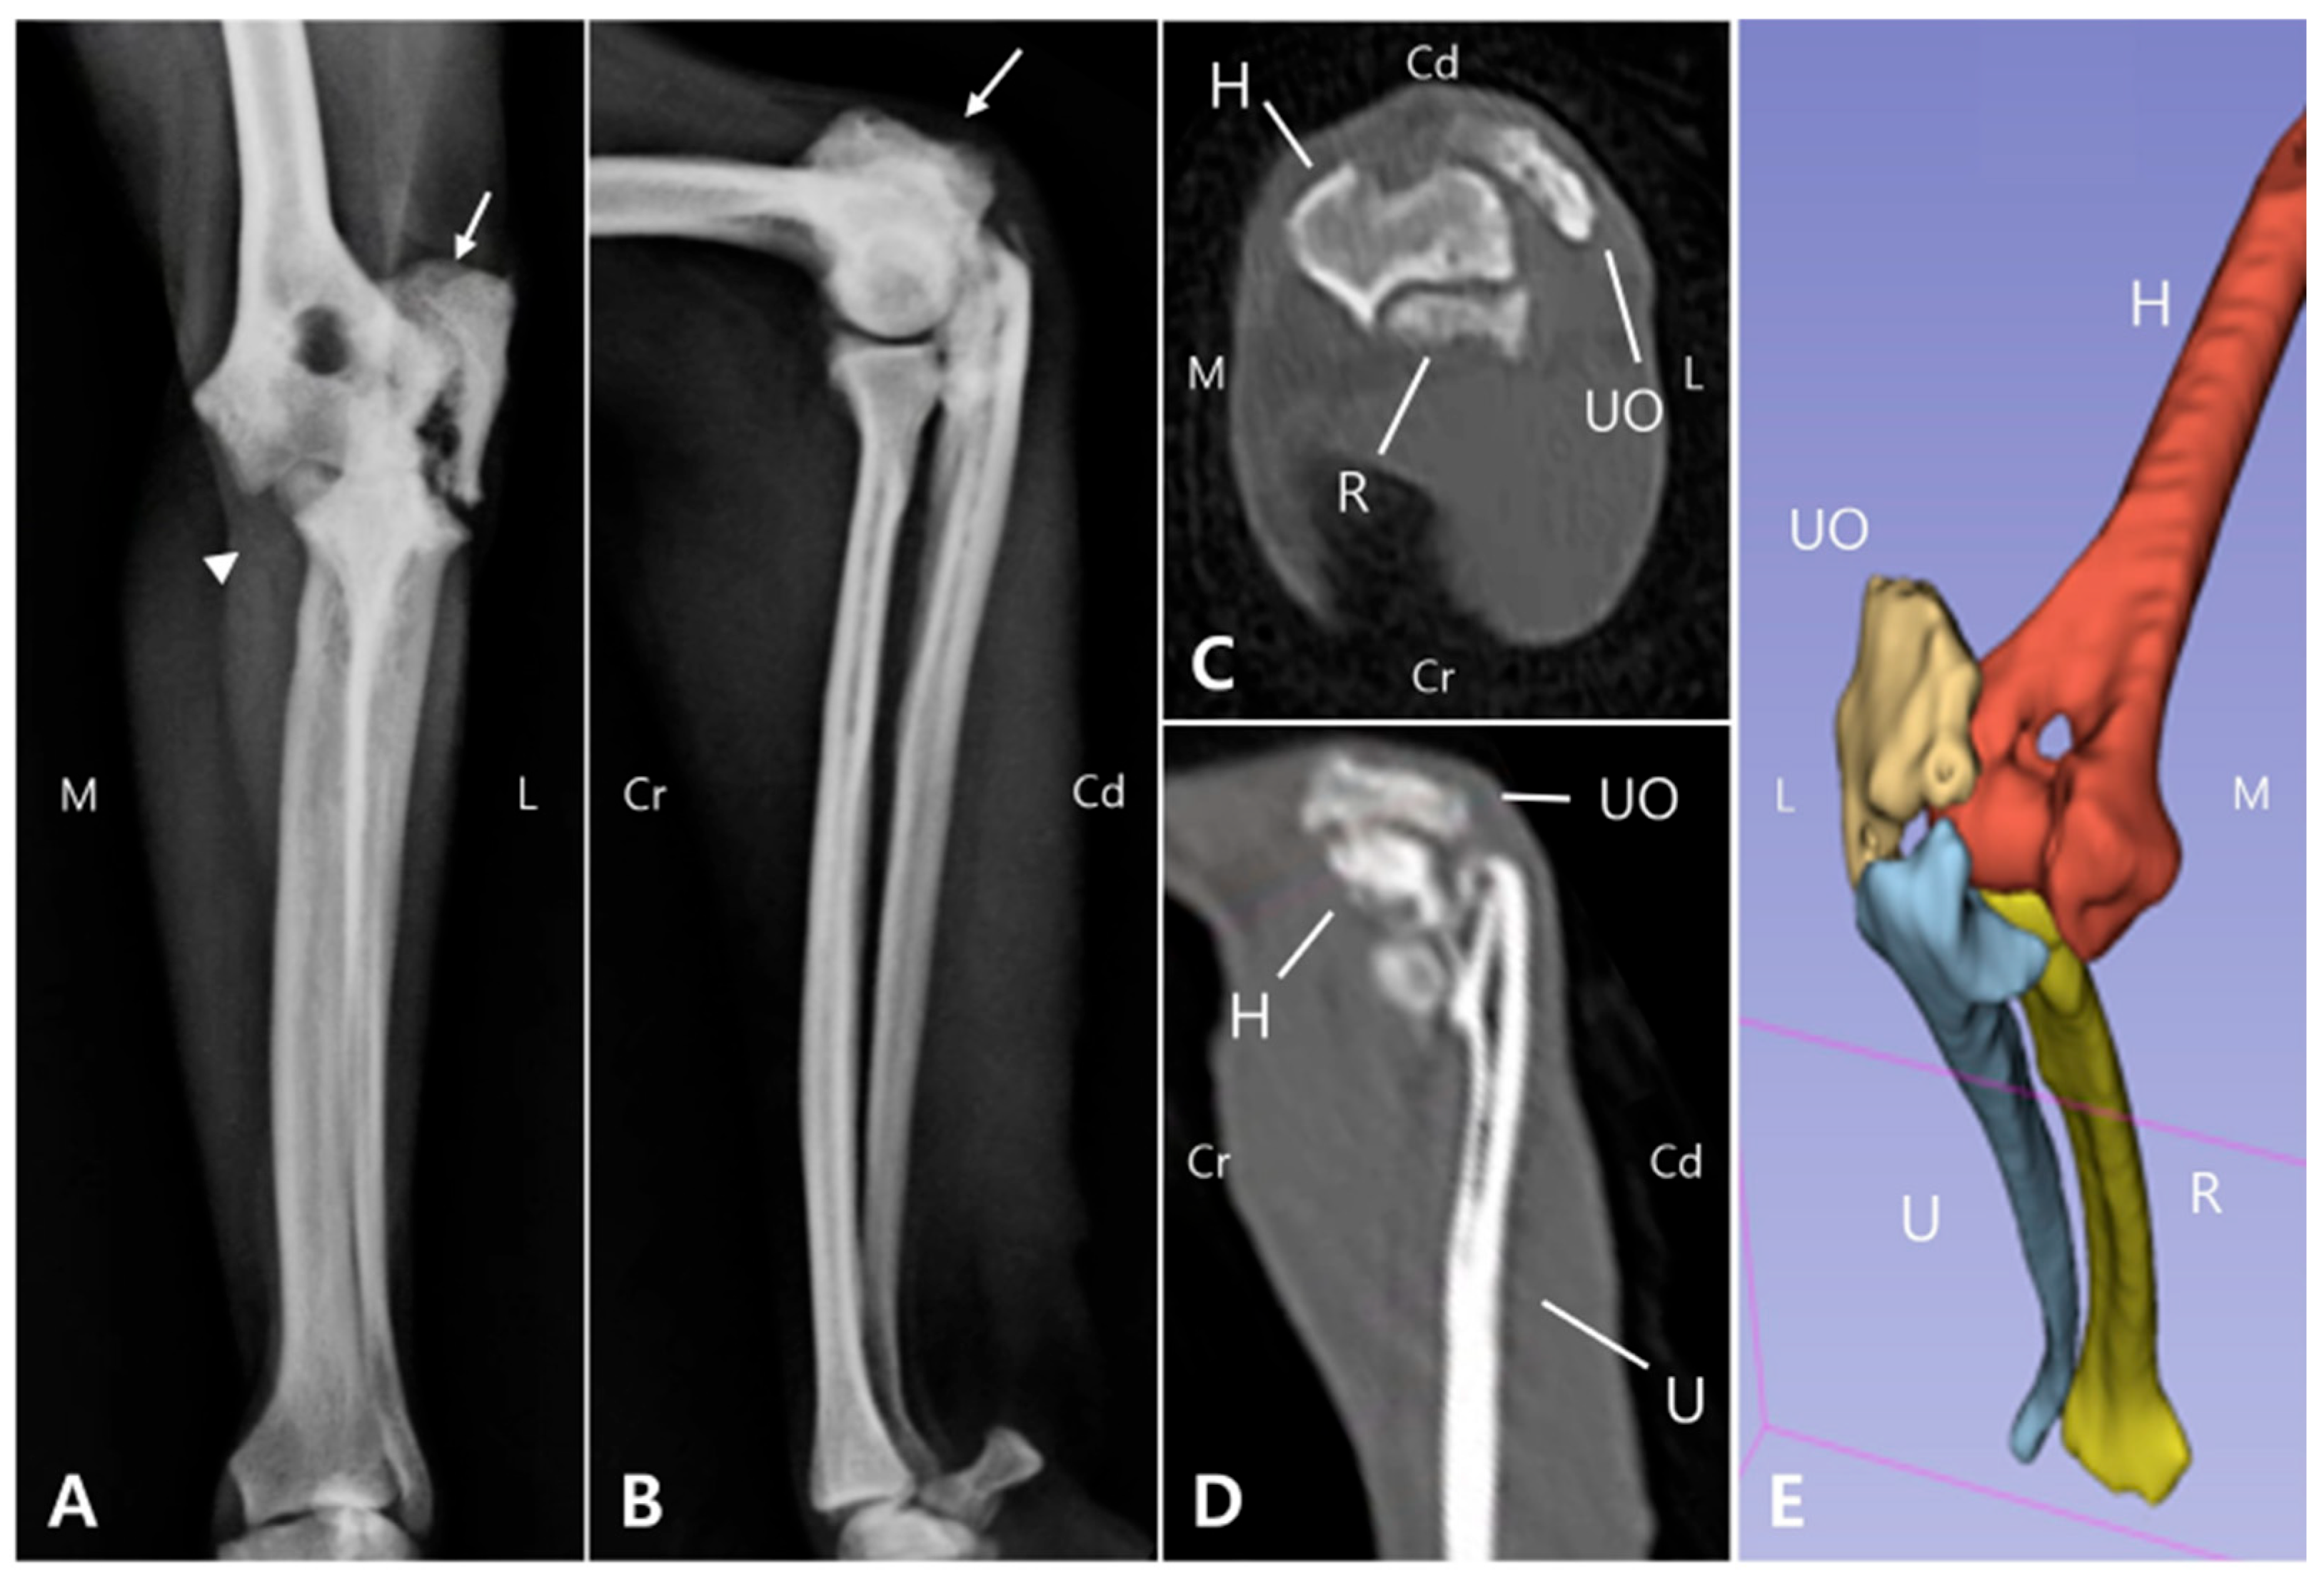

Two weeks postoperatively, the sutures were removed. Follow-up evaluations were subsequently performed including physical and orthopedic examination, gross gait analysis and radiography. The bandage was maintained for 30 days postoperatively as a means of coaptation to limit excessive joint motion, given the articular nature of the fracture and the associated ulnohumeral luxation. Although a transarticular external fixator could have been considered, this option was not pursued due to management challenges and financial limitations. By postoperative day (POD) 50, the patient was able to bear weight on the left forelimb during walking, with a lameness score of 3/5, although mild weight shifting was still observed [19]. Radiographs revealed a visible fracture line but reduced sharpness of the margin of the ulnar trochlear notch (Figure 5A). On postoperative radiographs, the anconeal process was not clearly identifiable, which was consistent with the gross appearance of 3D printed models (Figure 2 and Figure 5). On POD 140, the owner reported that the patient was fatigued easily during walks but was able to walk normally and showed satisfactory recovery. Gait evaluation performed at the hospital exhibited a lameness score of 0/5, with no observable lameness during walking or trotting [19]. Additionally, no pain response was elicited during palpating or passive range of motion the joint. The ROM of the left elbow joint improved to 40–140°, comparable to that of the right elbow joint (45–165°), and revealing significant improvement compared to the initial presentation (25–95°). These findings suggest that functional preservation of the joint was successfully achieved. Radiographs and CT images acquired at POD 140 confirmed progressive reduction of the fracture line gap (Figure 5B,C). Three-dimensional modeling reconstructed from CT data further demonstrated the stable positioning of the implants and restoration of anatomical alignment (Figure 5D). Follow-up information obtained from the owner confirmed that, as of 483 days postoperatively, the patient was doing well without any evidence of forelimb lameness.

Figure 5. Sequential radiographic and CT evaluation of fracture healing following plate fixation. (A) Medial view radiographs obtained on the day of surgery show appropriate plate placement with a clearly visible fracture line (arrow). (B) At 140 days postoperatively, the fracture gap appears reduced (arrow). (C) On the CT scan acquired at POD 140, the previously distinct fracture line is no longer discernible. (D) The 3D reconstruction generated from the CT dataset revealed the absence of the anconeal process. (H: Humerus; U: Ulna; R: Radius; Cr: Cranial; Cd: Caudal).